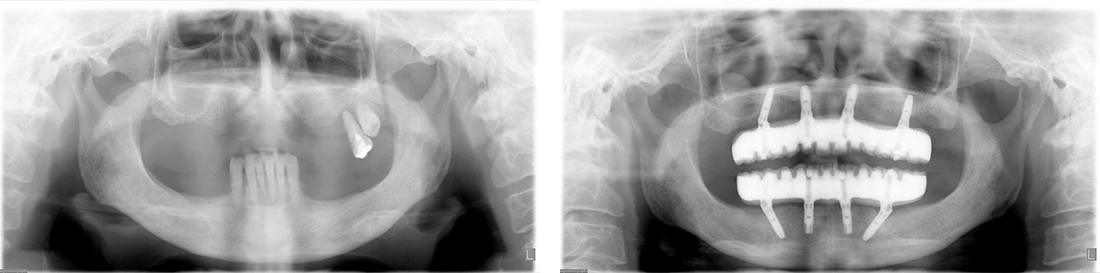

インプラント症例 Case1

Treatment cases

Before

After

インプラント症例 Case2